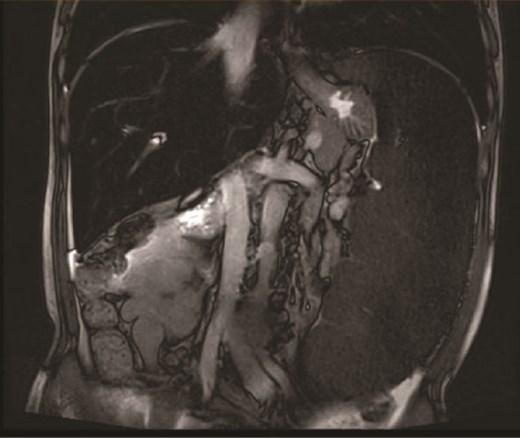

On the 19 August 2024, a 53-year-old man reported to our hospital complaining of “fatigue, jaundice, and abdominal discomfort for 10 years.” His hemolytic jaundice had been present for almost a decade. A family history of hereditary hemolytic jaundice was identified. His daughter and father both experienced similar ailments. Physical evaluation revealed that the skin and sclera were both stained by moderate yellowness. The left abdomen was full, and the spleen was hard and immovable, located 15 cm below the costal border. A computed tomography scan revealed that the spleen was 27.1 cm in length, 7.1 cm in thickness, and located 17.0 cm below the costal border (Figs. 1 and 2). The gallbladder measured 12.0 × 3.2 cm and contained several stones.

Because the patient exhibited evident signs of large splenomegaly, which was exerting a significant negative impact on his quality-of-life, we performed surgery on the 30 August 2024. Upon entering the abdominal cavity, we found no evidence of abnormalities in the liver, stomach, colon, small intestine, or mesentery. The spleen was enlarged, measuring ~35 × 20 × 10 cm3, with a pale appearance. The gallbladder measured ~10 × 6 × 4 cm3. Careful dissection of Calot’s triangle revealed the cystic duct diameter to be ~0.3 cm while that of the common bile duct was ~0.6 cm. The gallbladder was successfully removed. The splenocolic ligament was gradually dissected from the lower pole of the spleen toward the splenic hilum, exposing the splenic vessels and pancreatic tail. The gastrosplenic ligament was then dissected and exposed superiorly. Due to the massive size of the spleen, a decision was made to convert to open surgery. A midline upper abdominal incision, ~20 cm in length, was made, and the abdominal cavity was entered layer-by-layer. Then, we inserted a wound protector. Next, the short gastric vessels were individually dissected, clamped, and divided. The superior pole of the spleen was elevated, and the splenic ligaments were dissected, including the posterior splenorenal ligament. The dissection was completed by fully separating the splenic hilum, and the hilar tissues and vessels were divided sequentially to completely mobilize the spleen. The specimen was then removed intact. Subsequently, the abdominal cavity and operative field were thoroughly irrigated with warm saline. Inspection of the gallbladder bed, splenic fossa, gastric fundus, and vascular stumps confirmed no bleeding. Surgical gauze counts were correct. A 28# drainage tube was placed in the splenic fossa and exteriorized through the left trocar site. Another 28# drainage tube was placed in the Foramen of Winslow and exteriorized through the right trocar site. The abdomen was then closed layer-by-layer. Pathological examination (Fig. 3) revealed that the spleen was ~34 × 18.5 × 10 cm3 in size. Furthermore, the spleen had a smooth, slightly thickened capsule, a soft, grayish-red cut surface, vascular dilatation, congestion, and a few grayish-white streaks on the cut surface. The grayish-green gallbladder measured ~10 × 5 × 3 cm3, and there were several stones visible within. Microscopic analysis revealed thickening of the splenic capsule, widening of the splenic trabeculae, visible crystalline substances, a marked increase in red pulp and a reduction in white pulp, splenic cord congestion, splenic sinus dilatation, thickening of the vascular wall with fibrosis, and foreign body giant cell reaction (Fig. 4). The lymph nodes of the gallbladder showed signs of reactive hyperplasia. The patient was duly diagnosed with HS, hemolytic jaundice, hemolytic anemia, massive splenomegaly, and cholelithiasis with chronic cholecystitis.